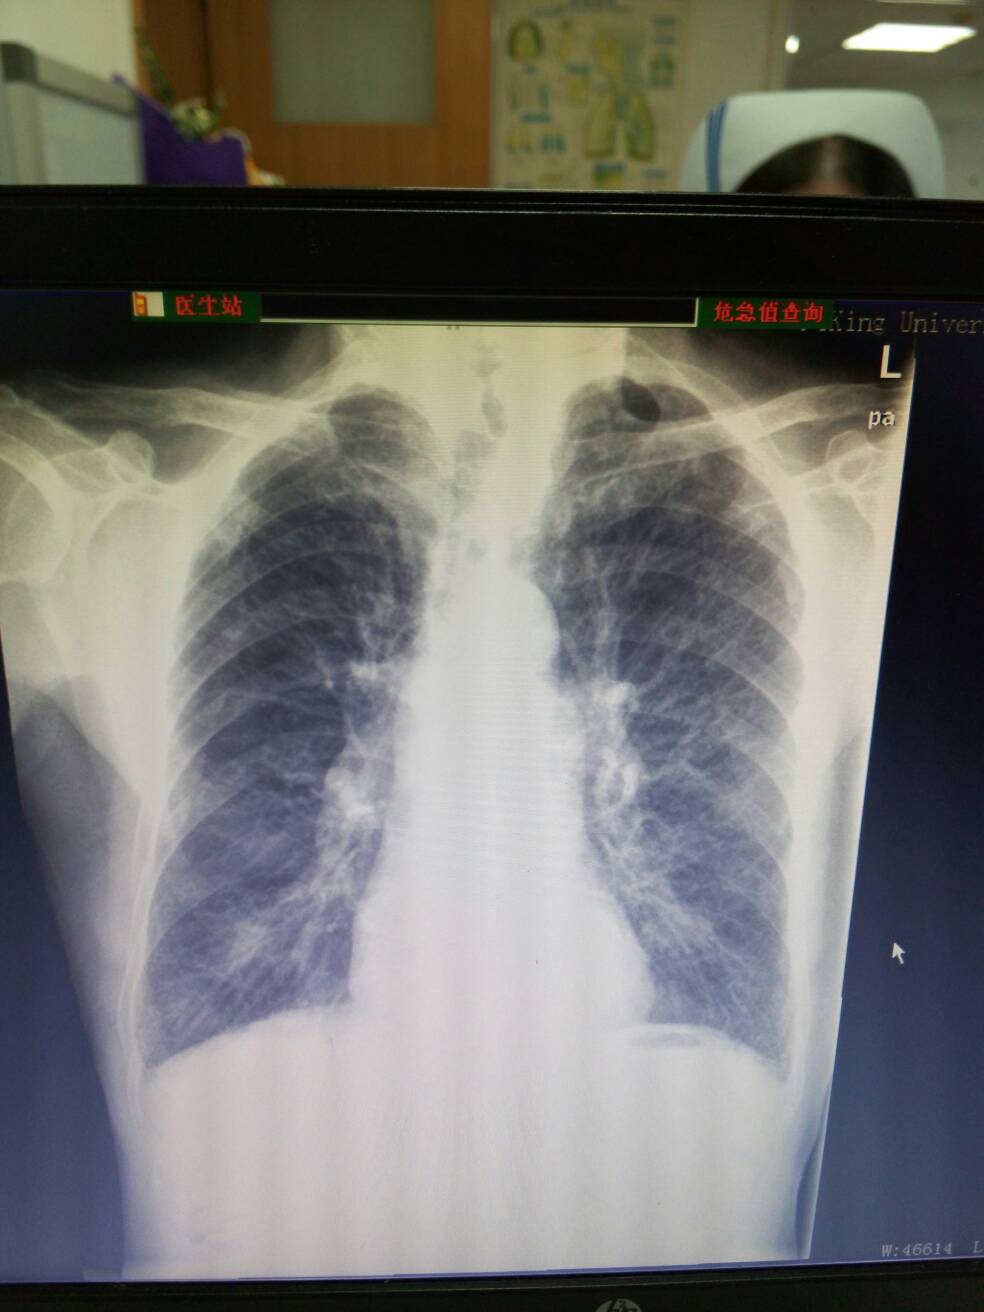

肺气肿 ( emphysema;pulmonary emphysema )